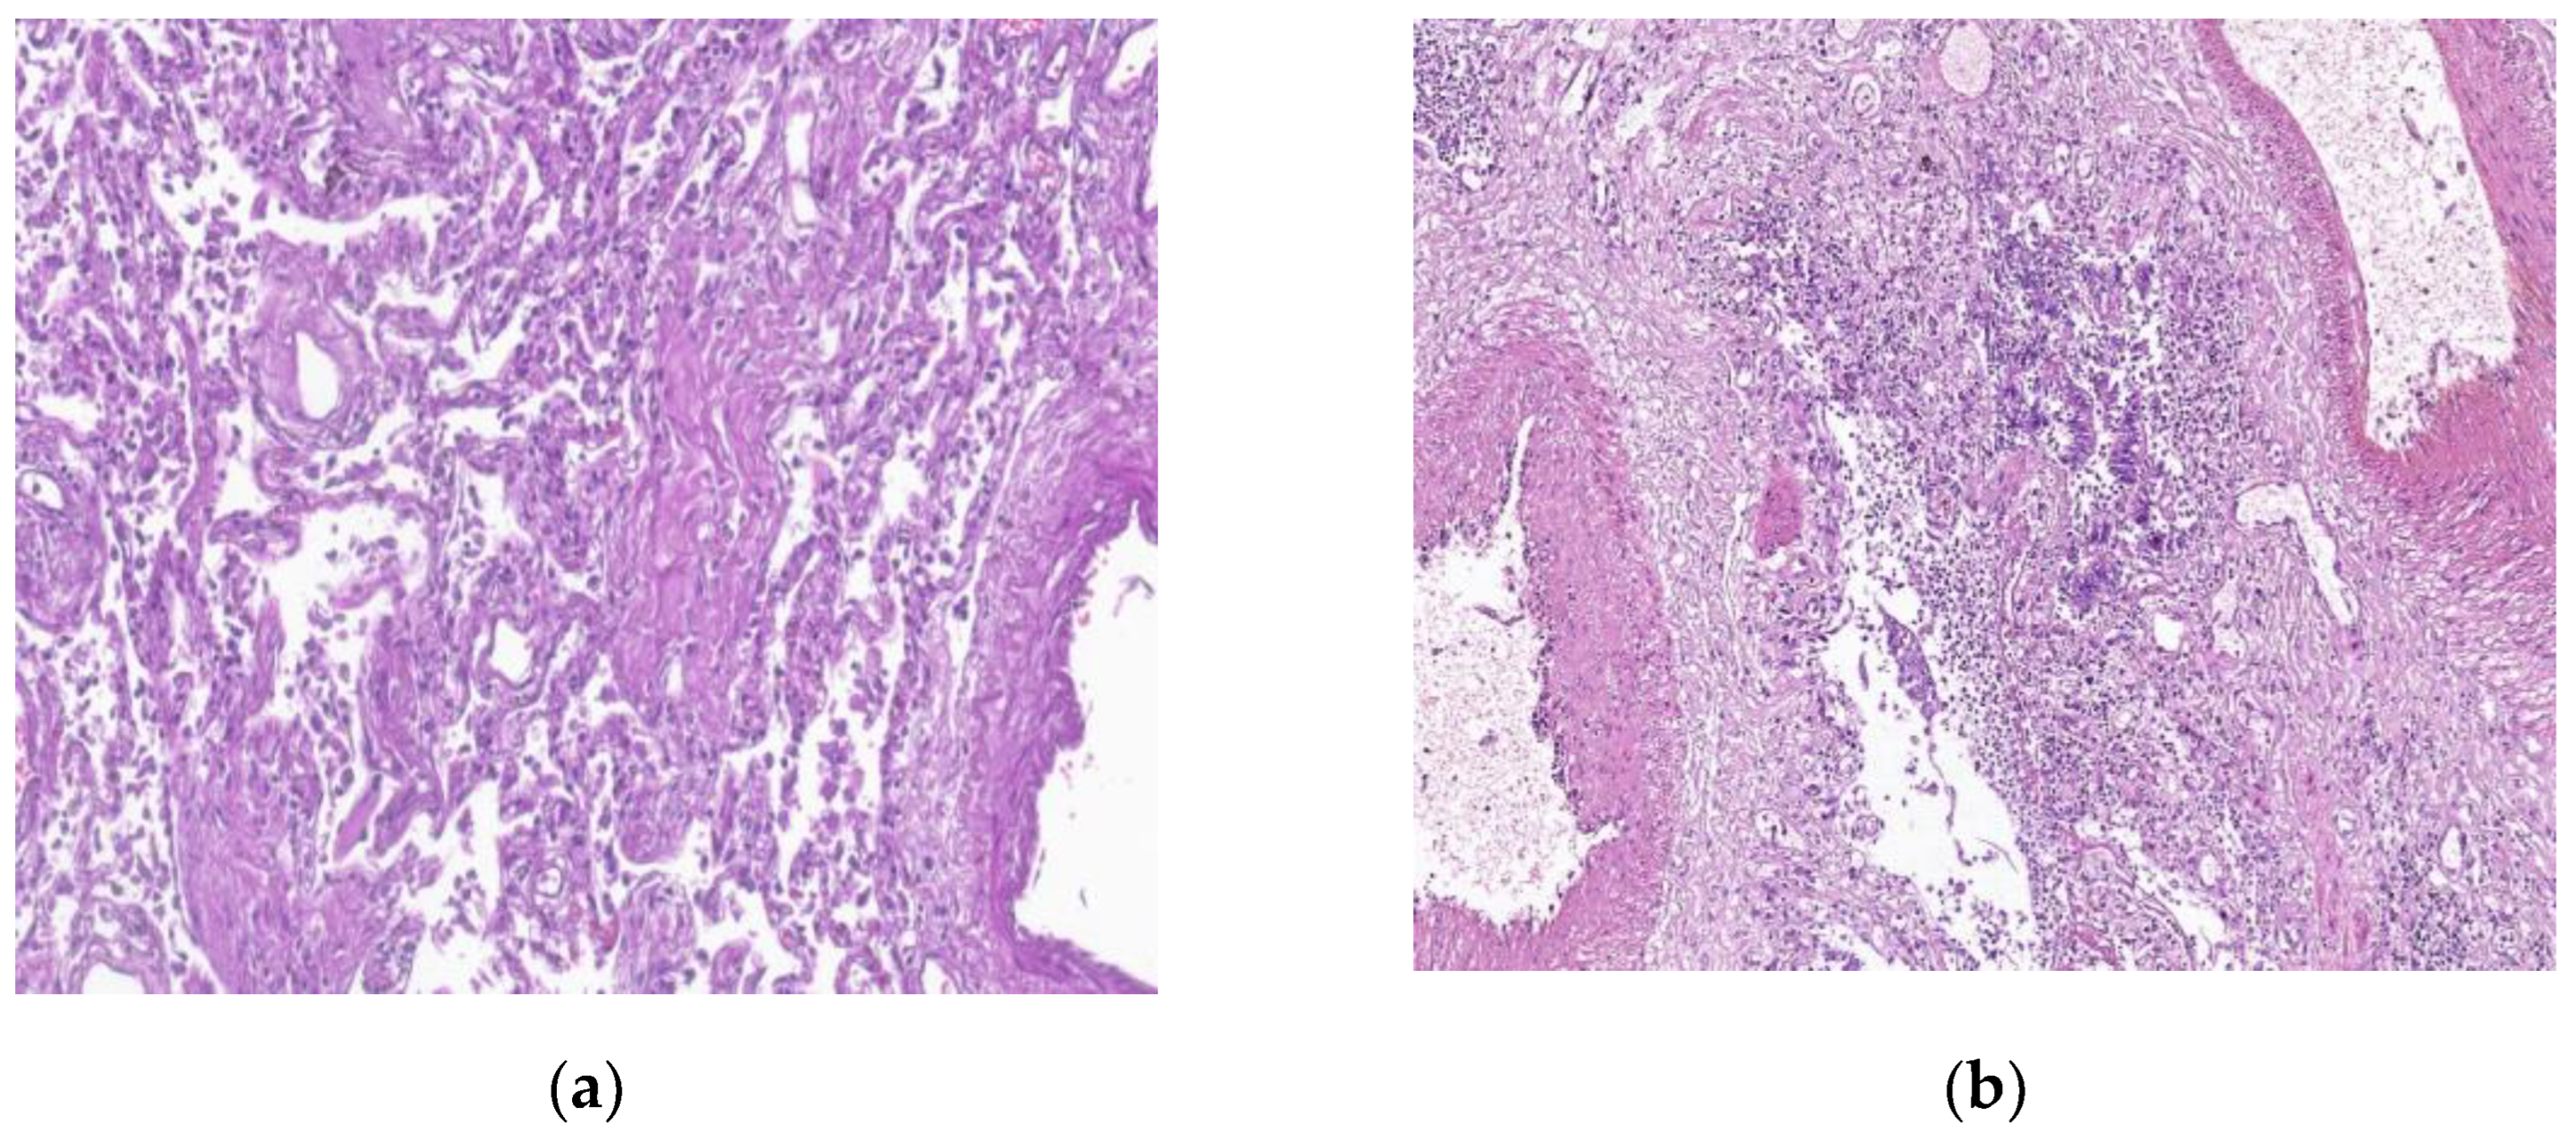

7. Histopathologic characterization

- Parambil, J.G.; Myers, J.L.; Aubry, M.-C.; Ryu, J.H. Causes and Prognosis of Diffuse Alveolar Damage Diagnosed on Surgical Lung Biopsy. Chest 2007, 132, 50–57. [Google Scholar] [CrossRef] [PubMed]

- Beasley, M.B.; Franks, T.J.; Galvin, J.R.; Gochuico, B.; Travis, W.D. Acute fibrinous and organizing pneumonia: a histological pattern of lung injury and possible variant of diffuse alveolar damage. . 2002, 126, 1064–70. [Google Scholar] [CrossRef]

- Tomashefski, J.F., Jr. PULMONARY PATHOLOGY OF ACUTE RESPIRATORY DISTRESS SYNDROME. Clin. Chest Med. 2000, 21, 435–466. [Google Scholar] [CrossRef]

- Li, Y.; Wu, J.; Wang, S.; Li, X.; Zhou, J.; Huang, B.; Luo, D.; Cao, Q.; Chen, Y.; Chen, S.; et al. Progression to fibrosing diffuse alveolar damage in a series of 30 minimally invasive autopsies with COVID-19 pneumonia in Wuhan, China. Histopathology 2020, 78, 542–555. [Google Scholar] [CrossRef]

- Zhang, H.; Zhou, P.; Wei, Y.; et al. Histopathologic Changes and SARS-CoV-2 immunostaining in the lung of a patient with COVID-19. Ann Intern Med 2020, 172, 629–632. [Google Scholar] [CrossRef]

- Kommoss, F.K.; Schwab, C.; Tavernar, L.; Schreck, J.; Wagner, W.L.; Merle, U.; Jonigk, D.; Schirmacher, P.; Longerich, T. The Pathology of Severe COVID-19-Related Lung Damage. Dtsch. Aerzteblatt Online 2020, 117, 500. [Google Scholar] [CrossRef]

- Copin, M.-C.; Parmentier, E.; Duburcq, T.; Poissy, J.; Mathieu, D. ; The Lille COVID-19 ICU and Anatomopathology Group Time to consider histologic pattern of lung injury to treat critically ill patients with COVID-19 infection. Intensiv. Care Med. 2020, 46, 1124–1126. [Google Scholar] [CrossRef]